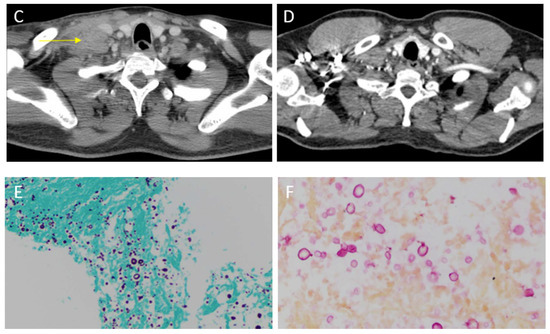

A 40-year-old Hispanic man presented to the hospital with headaches, dizziness, and progressive altered mental status for 1 week. His neurologic exam was significant for lethargy and neck stiffness. No focal deficits were noted. He was found to be infected with HIV. His CD4 count was 40 cells/μL, and his HIV viral load was 400,000 copies/mL. A lumbar puncture was performed and cerebrospinal fluid (CSF) analysis showed 15 white blood cells/mm3, a protein content of 60 mg/dL, and a glucose level of 20 mg/dL. The cryptococcal antigen from CSF was 1:512. A fungal culture from CSF isolated Cryptococcus neoformans. The patient was treated with 4 mg/kg/day of liposomal amphotericin and 100 mg/kg/day of flucytosine for 2 weeks (induction therapy). He developed marked improvement of his neurologic symptoms. Treatment was followed by consolidation therapy with 400 mg of fluconazole daily for 8 weeks. After 2 weeks of consolidation therapy, the patient started antiretroviral therapy, consisting of tenofovir alafenamide/emtricitabine, dolutegravir, and boosted darunavir (given the presence of the M184V mutation on the HIV genotype). After completing consolidation treatment, the patient was maintained on 200 mg fluconazole daily. He presented 15 months later with a painful neck swelling, fever, and chills. He stated that he had been compliant with HIV therapy and fluconazole. A physical exam revealed an enlarged and tender lymph node with purulent drainage in the supraclavicular region (A). To better characterize these findings and to evaluate extension into adjacent lymph nodes, we ordered a cervical computed tomography (CT) scan with contrast. This image showed a 6.2 × 4.3 cm heterogeneous mass (yellow arrow) anterolateral to the right scalene muscles, likely representing a conglomerate of necrotic lymph nodes (C). Laboratory studies showed a CD4 count of 227 cells/μL and an undetectable HIV viral load. He tested positive for serum cryptococcal antigen with a titer of 1:20. The patient was started on 15 mg/kg of vancomycin every 12 h and 1 g of ceftriaxone daily for a presumptive bacterial infection, and he continued with 200 mg of fluconazole daily. He underwent an ultrasound (US)-guided core biopsy of the lymph node. Histopathology showed granulomatous inflammation and necrosis with encapsulated pleomorphic round yeast with features suggesting Cryptococcus. Grocott’s Methenamine Silver stain highlighted the fungal elements (E). Their thick mucinous capsule stained bright red with mucicarmine special stain (F). Antibiotics were discontinued and the patient re-started induction therapy with liposomal amphotericin and flucytosine for possible cryptococcal relapse. He completed 2 weeks of induction therapy. After achieving significant clinical improvement, the patient was discharged with 400 mg of fluconazole daily. The final fungal cultures remained negative. At the 3-month follow-up, a physical exam showed near resolution of lymphadenitis (B). In addition, a CT scan showed a marked reduction in the necrotic mass (D). Cryptococcosis is a fungal infection typically associated with T-cell deficiencies, particularly acquired through immunodeficiency syndrome (AIDS), and it usually manifests as cryptococcal meningitis [1]. Although antiretroviral therapy has intensely reduced AIDS-related opportunistic infections, the restoration of CD4 cells can induce an immune reconstitution inflammatory syndrome (IRIS), characterized by a deregulated inflammatory response to specific infectious or non-infectious antigens. This response may lead to clinical deterioration caused by a previously unrecognized subclinical disease with viable opportunistic pathogens, which is known as “unmasking” IRIS. A similar process resulting from the worsening of a previously well-treated infection can also occur and is called “paradoxical” IRIS. In the latter, the pathogens are no longer viable, and cultures remain negative [2]. A wide extent of infections related to IRIS has been reported, of which cryptococcosis, tuberculosis, and Mycobacterium avium complex are the most common [3]. The overall incidence of IRIS associated cryptococcosis varies from 10 to 30%. It commonly presents as recurrent meningitis. Lymphadenitis is considered a rare event with only a few cases reported in the literature [4,5]. We believe our patient developed cryptococcal IRIS manifesting as lymphadenitis. His CD4 count markedly increased from 40 to 227 cells/μL after 15 months of antiretroviral therapy, which precipitated this inflammatory reaction. Our patient’s clinical presentation was consistent with the paradoxical type of IRIS, because it occurred while the patient was on effective antifungal therapy. Furthermore, despite visualizing fungal elements in the histopathology, no viable organisms were obtained from cultures. The treatment of this condition depends on the type of IRIS. For unmasking cryptococcal IRIS, the treatment is standard antifungal therapy. On the other hand, paradoxical cryptococcal IRIS does not require a new course of induction and consolidation therapy, because the pathogens are no longer viable. Many clinicians end up giving standard antifungal therapy while waiting for negative cultures [6], which also occurred in our case. Adjunctive therapy with steroids can be considered in patients with severe paradoxical responses. Discontinuation of antiretrovirals is not recommended [7]. In our patient, anti-inflammatory medications were not needed. A similar case of cervical lymphadenitis by Cryptococcus was described by Bhuyan et al. [8]. They achieved a definite diagnosis by fine-needle aspiration of the involved lymph node and subsequent histopathological examination. The characteristic capsule of Cryptococcus is used as a diagnostic tool. The hematoxylin-eosin and Nigrosin stains create a negative image, visualizing the thick capsule as a clear halo on a dark background. Other special stains used in the laboratory to visualize the gelatinous capsule are mucicarmine and methenamine silver stains [8]. Our case highlights the importance of considering cryptococcal-related IRIS in the differential diagnosis of lymphadenitis in HIV-infected individuals. We advocate the use of US-guided biopsy of affected lymph nodes and tissue cultures for accurate and prompt diagnosis of this condition. Resolution of symptoms generally occurs with conservative therapy and continuation of antiretrovirals.